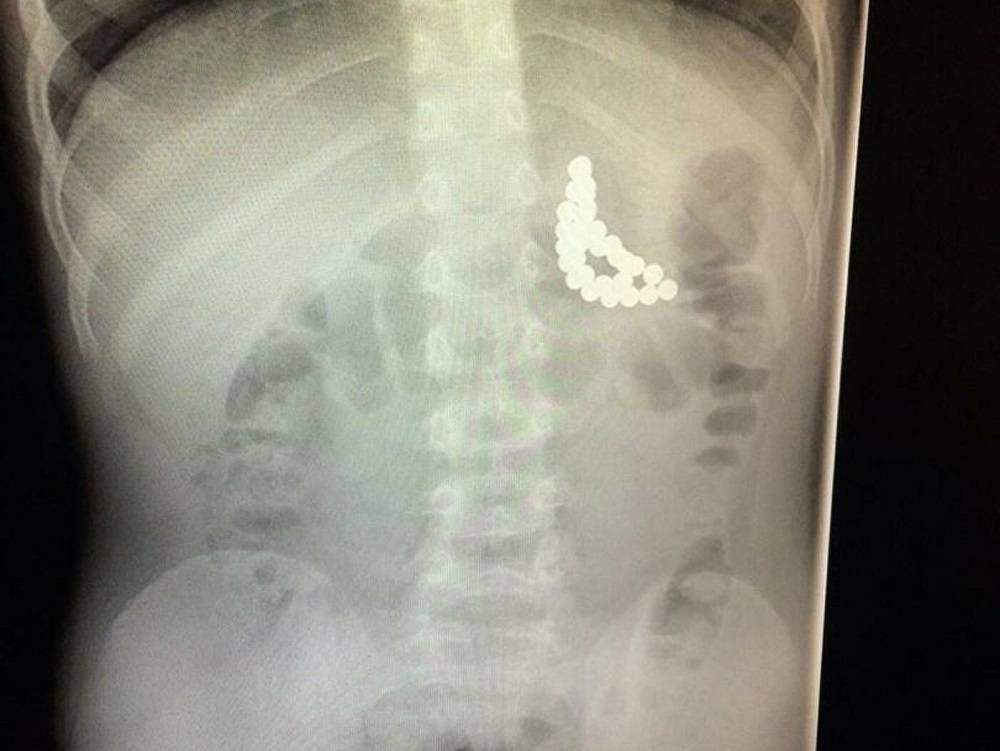

Клинический случай

Типичный пример описанной ситуации: здоровый мальчик трех лет был доставлен в отделение неотложной помощи, его мать обеспокоена тем что «он проглотил несколько круглых магнитов». Единственным симптомом, выявленном при осмотре ребенка – была гиперсаливация. На обзорной рентгенограмме брюшной полости врачи увидели, что магниты расположились в эпигастральной области и правом нижнем квадранте живота. Было выполнено эндоскопическое исследование проксимального отдела тощей кишки, в надежде найти там магнит, однако за время подготовки ребенка к процедуре – магнит сместился за пределы досягаемости эндоскопа. Ребенок отпущен домой, маме даны рекомендации осматривать каловые массы ребенка, искать и считать магниты, пока не выйдут все. Кроме того, ребенку был назначен курс слабительного.

За два дня, несмотря на диарею от слабительного, в стуле не было найдено ни одного магнита. Кроме того, у ребенка появилась лихорадка, тахикардия и боль в животе. Повторная рентгенограмма показала, что магниты соединились в правом нижнем квадранте брюшной полости. При лапароскопии выяснилось, что 3 неодимовых магнита, «приклеившись» друг к другу, вызвали перфорацию двух петель подвздошной кишки. Магниты были удалены, перфорации ушиты.